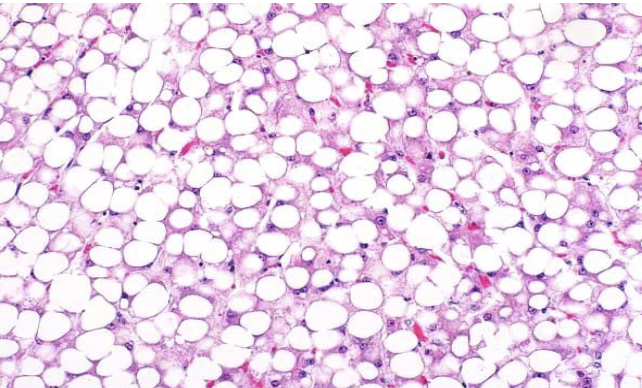

what does the image show?

lipid type VH

what type of hepatocellular accumulation is characterized by discrete vacuoles that push the nucleus to the periphery?

lipid VH